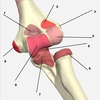

201

apex of the cubital fossa radial/ulna

1

203

radial fossa of humerus

3

205

capitulum of humerus

5

207

radial head

7

209

trochlea of H

9